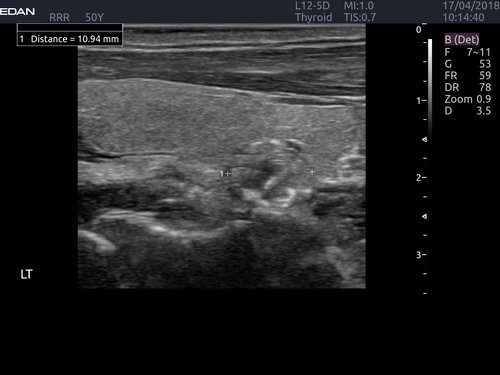

Modernes Farbdoppler Ultraschallgerät

Edan Acclarix LX4 Beschreibung

Das Ultraschalldiagnosesystem Acclarix LX4 bietet einen hervorragenden Wert und hervorragende Bildqualität in umfangreichen Anwendungen.

Definitive Bildqualität

• Hohe Kanaltreue und hohe Kanalanzahl

• Tissue Adaptive Imaging (TAI) kontinuierlich und automatisch optimiert die Bildgebung, um mehr Fokus auf den Patienten zu ermöglichen

• B-Modus: TAI fein stimmt mehrere Parameter für optimale Bildgebung ab

• Doppler: TAI passt sich dem Durchflusszustand an Verbesserte Kontinuität, Grenzerkennung und Ausfüllen

• Speckle-Reduktionstechnologie (eSRI)

• Spatial Compounding-Bildgebung (SCI)